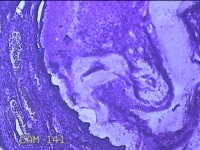

宫颈赘生物

性别

女

年龄

49岁

临床诊断

人乳头瘤病毒感染

一般病史

宫颈HPV阳性TCTLSLL

标本名称

大体所见

灰白粉红色肿物1.2x0.8x0.2cm两个,表面光滑。